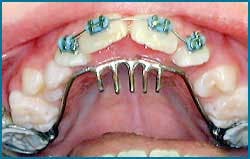

Palatal rake for cessation of thumb sucking (Image provided by Great Lakes Orthodontic Lab)